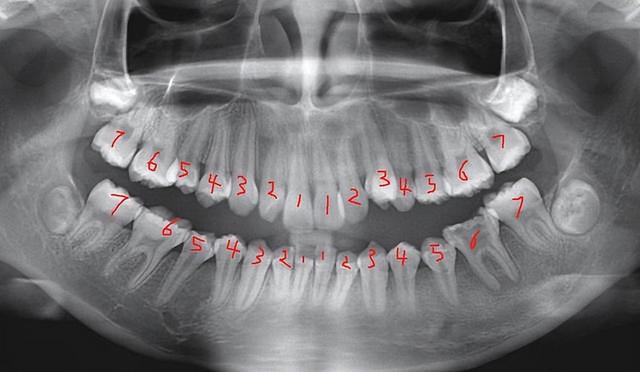

普通人一生一般都有两副牙齿,一副是乳牙,一副是恒牙,乳牙一般有20颗左右,从出生之后6个月是2岁之间,乳牙会逐渐地萌出。

20颗乳牙,包括乳前牙,乳尖牙,还有乳磨牙,中切牙是两颗,侧切牙是两颗,尖牙是两颗,磨牙一共是4颗,这是上颌的牙齿。

下颌的牙齿有中切牙2颗,侧切牙2颗,尖牙2颗,磨牙4颗,这是乳牙牙列。6岁以后恒牙开始萌出,乳牙脱落,一般萌出到13-14岁,形成恒牙列。

恒牙一般是28-32颗牙齿,上颌的牙齿有2颗中切牙,2颗侧切牙,2颗尖牙,4颗双尖牙,4颗磨牙,还有2颗智齿。下颌的牙齿有4颗切牙,2颗尖牙,4颗双尖牙,还有4颗磨牙,以及2颗智齿。